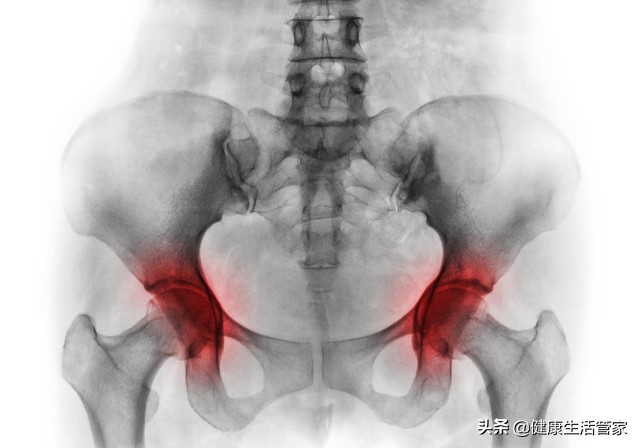

01、股骨头坏死的治疗

股骨头坏死的治疗分为早期治疗和晚期治疗。

02、股骨坏死能治好吗

股骨头坏死一旦发生,其内部的骨细胞和骨小梁已经坏死,并不可再生。股骨头坏死发生后,其内部有相应的修复过程,这种修复的过程即为骨头的增生过程,最后可导致股骨头的塌陷、骨性关节炎、股骨头和髋臼的增生。

所以股骨头坏死只能通过及时有效的治疗,阻止或延缓其病情的恶化,并不能中止其发展,或完全治愈恢复为坏死之前的状态。

03、股骨坏死怎么治

股骨头坏死是临床中一种常见疾病,其发生、发展的过程缓慢。在临床中分四期,每一期的治疗方法都不同。